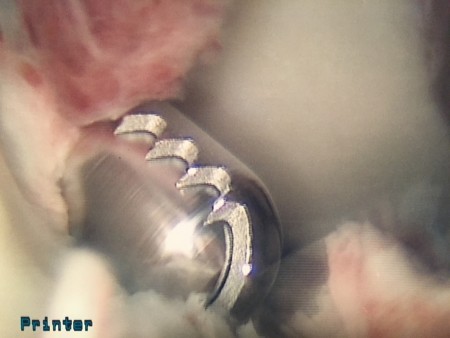

- Dr. Steadman found using a heat probe called an ArthroCare Wand allowed him to precisely address offending scar tissue by burning and releasing it. (Pardon the notes on the images.)

- Arthrofibrosis surgery is the intersection of medicine and art. Your doctor needs to have the experience to carefully and gently identify aberrant scar, address it, and leave non-symptomatic scar alone.

- Drs. Steadman and Singleton finish each surgery by slowly decreasing the saline pump pressure, thereby decreasing the pressure inside the knee joint, and looking for bleeding. Using the ArthroCare Wand allows them to cauterize any bleeding before the knee is closed.